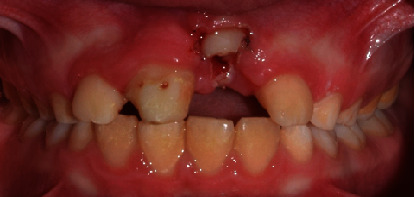

A 10-year-old boy presented to the endodontic department at the Faculty of Dentistry, King Abdul Aziz University, roughly 3 hours after sustaining a traumatic injury to his maxillary anterior teeth and upper lip (Figure 1). The trauma occurred after he fell on his face while playing football at school. His medical history was reviewed and found to be insignificant.

Extraoral picture of the patient at the time of arrival.

Upon clinical examination, the patient was noted to have a swollen upper lip and multiple gingival lacerations. Multiple tooth fragments were found to be loosely attached to the gingiva and both maxillary central incisors incurred complicated crown-root fractures during the injury (Figure 1). Intrusion was suspected but could not be confirmed clinically due to the severity of the trauma. The traumatized teeth were tender to percussion and palpation, but no alveolar bone fracture could be detected. The sensibility test revealed vital lateral incisors and primary canines. The lower anterior teeth were unremarkable and showed no injury.